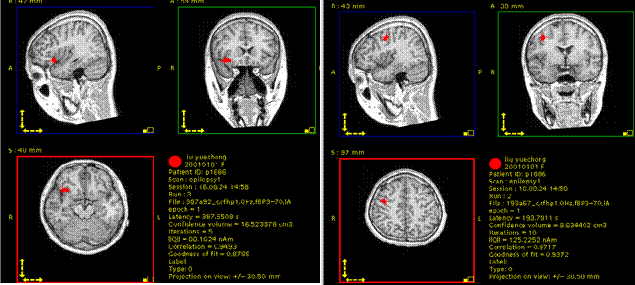

脑磁图:发作间期癫痫灶位于右侧额叶及中央区可能性大

经科室病例讨论,外六科吴杰主任考虑患者癫痫灶位于右侧额颞部可能性大。为精确定位癫痫灶,几日后,医生全麻下行“右侧额颞顶深部电极置入术”。共植入11根脑深部电极。

术后监测记录立体脑电图(SEEG),记录到多次发作事件,明确了癫痫灶起源位置及癫痫放电的传播路径。

根据脑电图记录的结果,患者癫痫为右颞起源,向右额传导。半月后在局麻下行“右额颞癫痫灶颅内电极毁损术”。毁损右颞癫痫灶过程中患者有短暂而轻微的局灶性癫痫发作一次。手术过程顺利,术中、术后小刘无不适感。术后无功能障碍。

术后复查MR图像,传入导航系统,与之前的计划融合,见毁损灶定位精确。患者恢复迅速而良好,至今无癫痫发作。